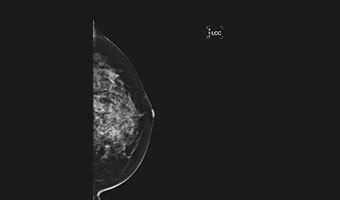

低剂量高清图像

微小病灶,清晰呈现

放大摄影功能,微小病灶无处遁形

低剂量高清晰兼顾

进口钼靶球管 X射线更适合乳腺检查 管球寿命更高 钼铑双滤过,根据乳房致密度自动智选

先进的乳腺成像算法